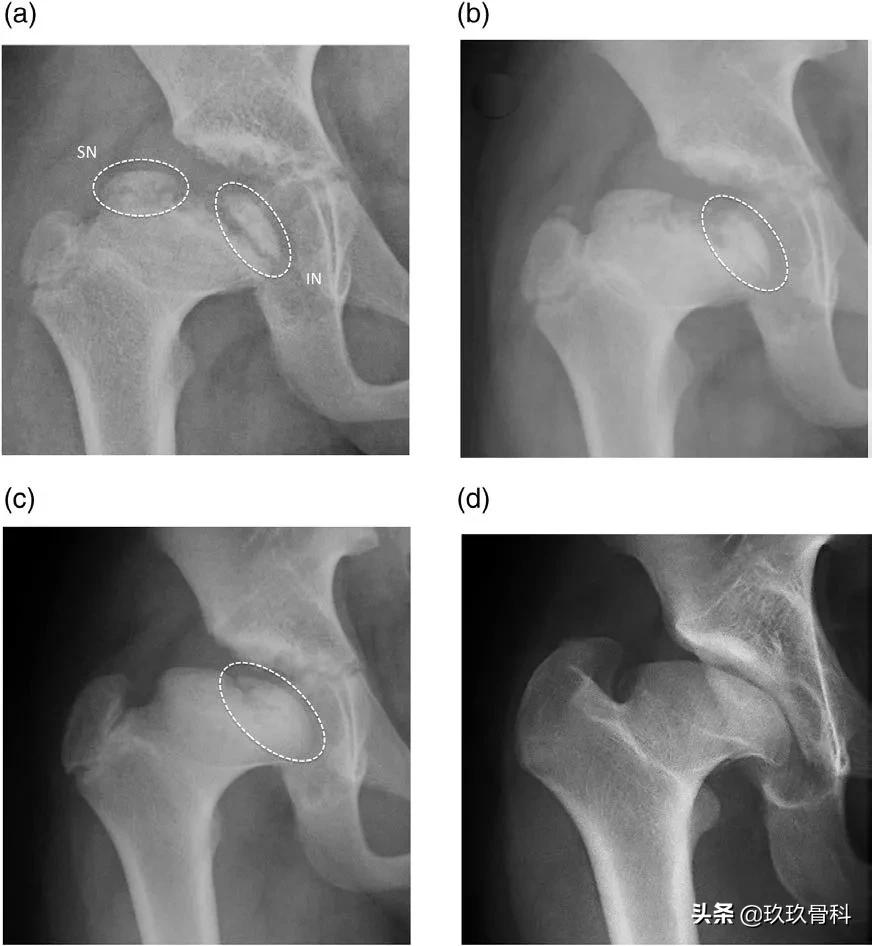

图1. (a)在髋关节前后位片上进行的测量。SND,上颈部距离;IND,下颈部距离。D:股骨头的直径;H:股骨头骨骺中央部的高度。(b)在两个骨骺端二次骨化中心的中央区域没有骨化。IPA,骨骺生长板内角;IN,下核(二次骨化中心);SN,股骨头骨骺的上核。

图2. 髋关节前后位X线片显示椭圆形过程。(a)在骨化开始的当年进行X线片检查。观察到两个独立的骨骺端二次骨化中心。上核下方的骨骺消失了。(b)前方X线检查。在上骨骺端二次骨化中心的底部几乎观察到上半球的完全缩小。下骨骺端二次骨化中心的下半体保持开放。(c)2年时对前方进行X线检查。上核与干骺端融合在一起,而下核继续具有可见的骨骺形态。两个二次骨化中心之间的中央区域仍未骨化。(d)最终的Stulberg阶段IV结局,其中央扁平化、过度外凸和与大转子相关的过度生长。IN,下核;SN,上核。